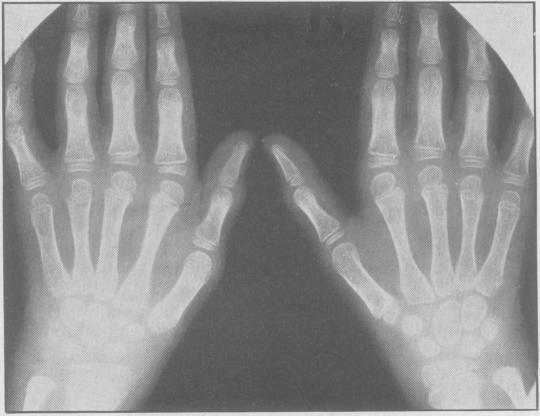

Juvenile rheumatoid arthritis (Still's disease).